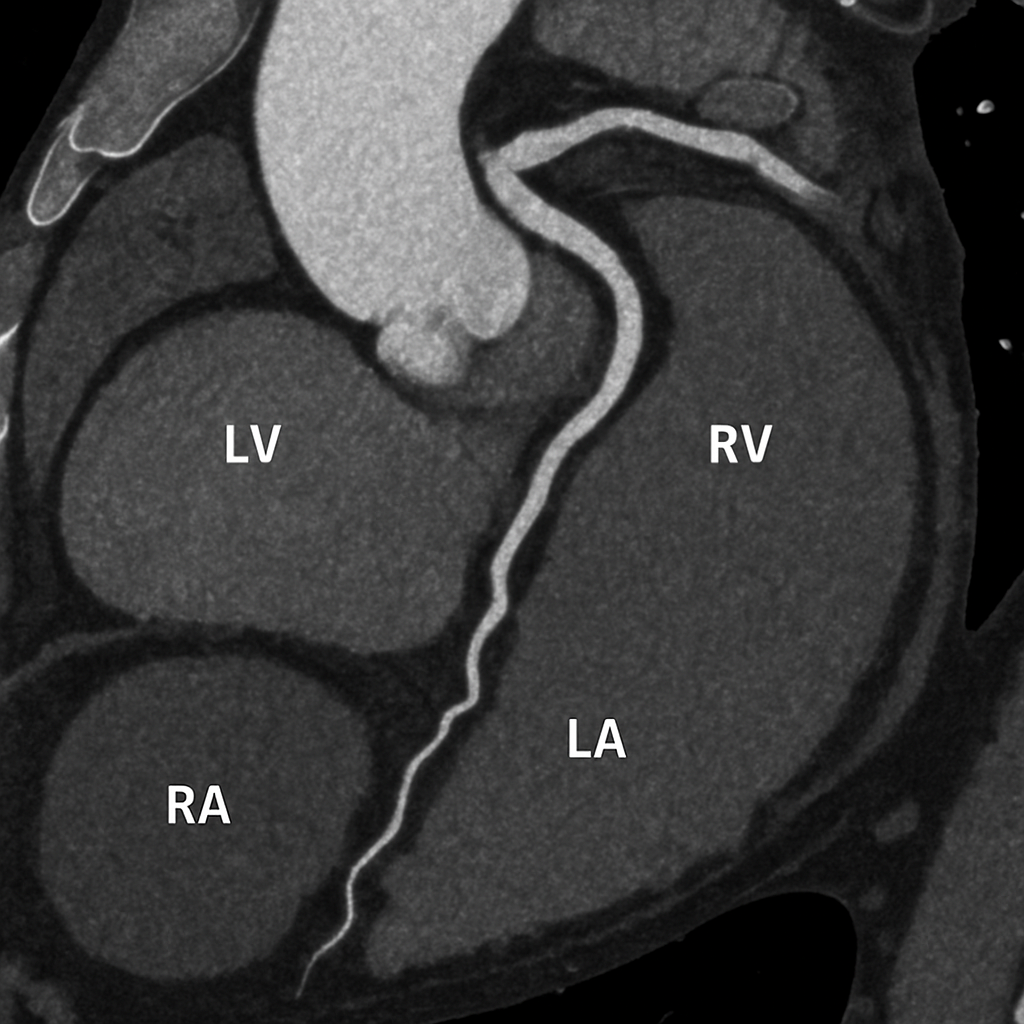

Cardiac phantom with myocardium, chambers, valves, and coronary arteries

AI-generated comprehensive cardiac phantom with all four chambers, valves, coronary arteries, great vessels,...